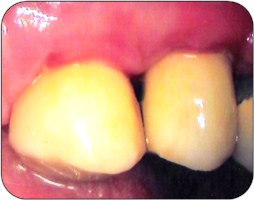

Einsetzen der Zirkonkeramikkronen (Juni '10)

fertiges Ergebnis nach der Wundheilung |